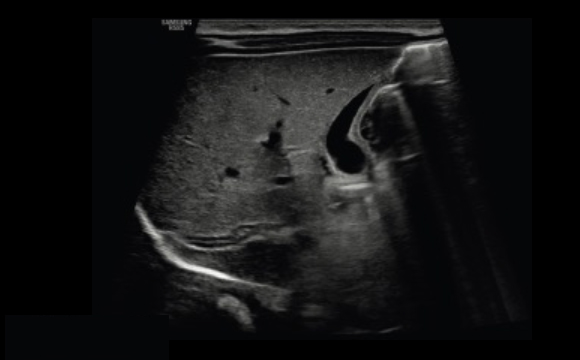

Anspruchsvolle Bildverarbeitung

Verborgene Strukturen sehen

ShadowHDR™ wendet selektiv hohe und niedrige Frequenzen des Ultraschalls an, um Schattenbereiche zu identifizieren und ermöglicht dadurch ein verbessertes Bild.

Neonataler Kopf a

Abdomen a

Unscharfe Bereiche im Bild reduzieren

Der Bildverbesserungsalgorithmus HQ-Vision™ dient der Reduktion von Unschärfe zur Unterstützung der Bildqualität.

Rauschunterdrückung zur Anpassung des 2D-Bildes

ClearVision ermöglicht anwendungsspezifische Anpassung und erweiterte zeitliche Auflösung im Live-Scan-Modus. Der Rauschunterdrückungsfilter unterstützt dabei die Kantenverstärkung und erzeugt scharfe 2D-Bilder für eine präzise Diagnose.